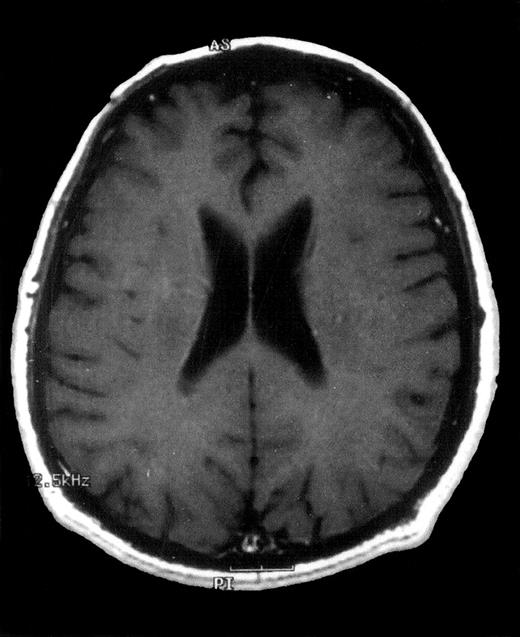

Axial contrast-enhanced T1-weighted MRI image of the brain 12 months after diagnosis.

Complete disappearance of intracerebral lesions after treatment with oral itraconazole.